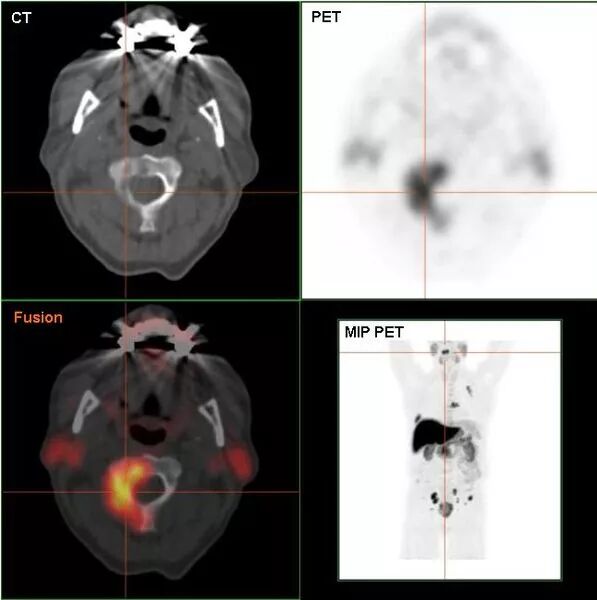

再有,鸡蛋富含胆碱(卵磷脂)。临床上在不同组织的癌症中,发现胆碱浓度提高。胆碱浓度升高可能与癌症恶化转移的过程相关。这个特点已经被应用到癌症的检测当中。正电子标记的胆碱被患者服用后能可靠地在PET-CT造影中标识癌组织。